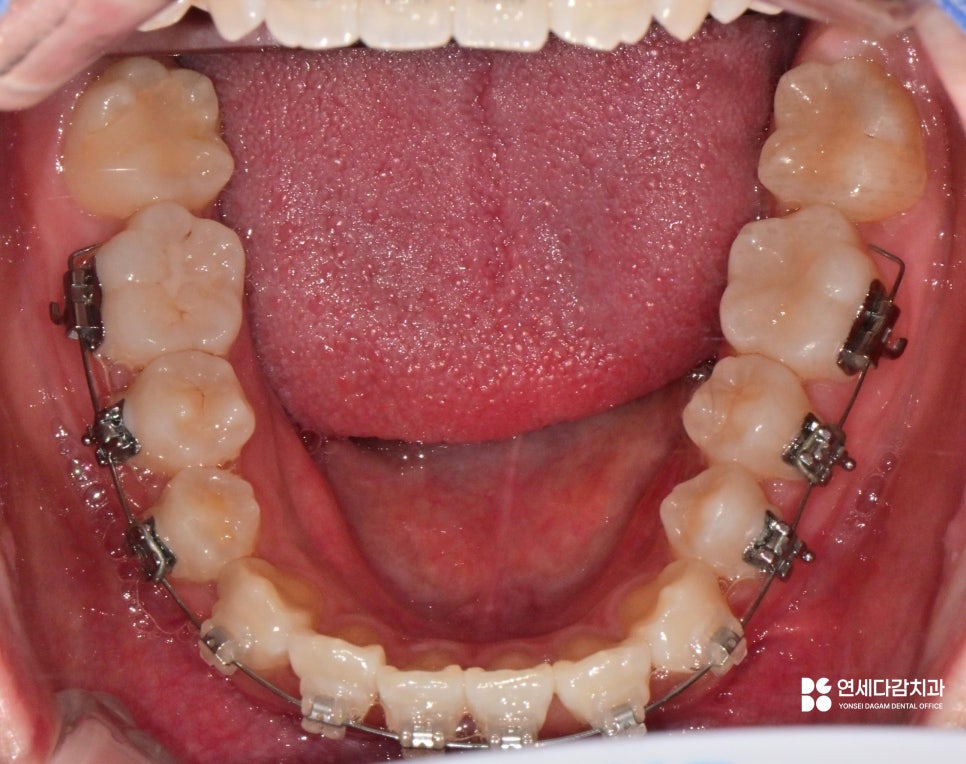

가락동 치과 에서 설명하는 케이스는

교합면이 혀쪽으로 향해 있으며,

진료 접근을 위해서는 잇몸 절개 후

골 삭제가 필요할 것으로 판단됩니다.

특히 아래쪽 사랑니처럼 주변 조직에

불필요한 영향을 줄 수 있는 케이스는

사전에 방지할 수 있는 전략이 됩니다.